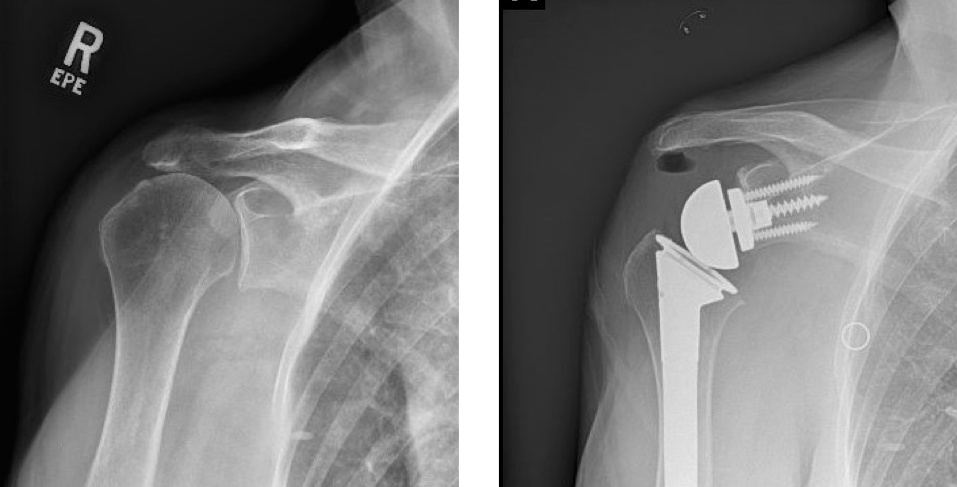

Pre-operative and post-operative xrays of a patient with rotator cuff tear arthropathy, treated with reverse total shoulder.

The reverse total shoulder was developed to help patients who have rotator cuff tears and shoulder arthritis. With a damaged rotator cuff, conventional anatomic total shoulder arthroplasty implants wear out too quickly. A reverse total shoulder involves replacing the ball and socket joints; however, the ball is moved to the "socket" side, and the "socket" is placed on the ball or humeral head side. This medializes and distalizes the center of rotation, allowing the deltoid muscle to raise the arm.

Although initially the reverse total shoulder was used for patients with shoulder arthritis with rotator cuff tears, it can also be used successfully in patients with shoulder arthritis who have significant glenoid or "socket" bone loss, complex proximal humerus fractures, chronic dislocations, revision of anatomic total shoulders, massive irreparable rotator cuff tears, and patients at high risk of developing rotator cuff tears with arthritis (advanced age, rheumatoid arthritis, etc.).